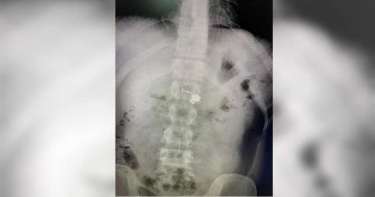

近日越南一位民眾發生一件搞笑的意外,這位民眾在半夢半醒間,竟然把手上的AirPod無線耳機,當作藥物直接吞下肚,直到清醒後才意識到釀成大錯,急忙跑到醫院求助於醫生。根據《中國報》報導指出,這名民眾表示,他時常與女朋友通宵視訊聊天,很有可能是在睡著的時候,就這樣把AirPod從耳朵拿下放在手上而不自知。而在當天凌晨5點30分左右,他的母親拿藥物來給他服用,而這位民眾就在半夢半醒間,把藥物跟耳機直接搭配開水全部吞進肚子內。而此時的他,還覺得今天的藥丸怎麼這麼大顆,有點難吞。後來在他睡醒後,他才意識到,自己竟然把AirPod當作藥物給吞下,急忙跑到醫院求助於醫生。在X光的檢查下,真的確認這位民眾的體內有個AirPod的耳機,最後醫生透過手術的方式,幫這位民眾的AirPod從肚子裡面取出。

男呼吸困難急就診! 醫一看X光嚇傻:怎麼有AirPods

美國麻薩諸塞州一名38歲男子日前起床後感到呼吸困難,本以為喝點水可以舒緩不適,沒想到卻頻作嘔,趕緊前往就醫,一照X光讓醫生嚇壞,他的食道中竟有一隻AirPods耳機。綜合外媒報導,38歲男子布拉德·高迪耶(Brad Gauthier)日前起床後感到身體不適,他試圖喝水舒緩,但仍感到呼吸困難,有快窒息的感覺,於是前往醫院就診。一開始,醫護人員認為布拉德不適的原因可能與前一天妻子生日宴會上的食物有關,沒想到一照X光,才發現他的食道中有一隻AirPods耳機,讓醫護人員都嚇壞。布拉德表示,自己都會戴著AirPod耳機睡覺,推測可能是在睡夢中不知不覺把耳機吞了下去,所幸他趕緊到醫院檢查,進行手術將耳機取出,才沒有造成身體的損傷,休息一段時間後,也能夠照常吃東西。布拉德說,「如果我吸了它,或者它已經滯留或限制了我的呼吸道,那肯定是一件更加嚴重的事情。」並表示自己真的很幸運,可以很快地找到問題並解決,他也對醫護人員表示感謝,也透露雖然被吞下的耳機還能運作,但麥克風功能已經壞掉了。